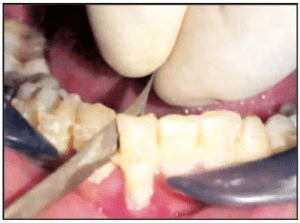

Đĩa corborundum một mặt nhẵn

Loại này được sử dụng để mài sơ khởi. Nhưng vấn đề vốn có là cứng và giòn, có khả năng cao bị gãy và làm tổn thương bệnh nhân cũng như bác sĩ. Loại này khó sử dụng ở vùng răng sau.

-